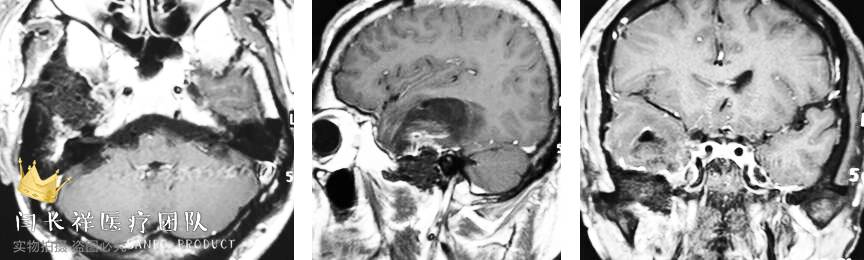

术前MRI轴位T1增强示病灶显著不均匀强化。

中颅窝-颞下窝占位

术前MRI矢状位T1增强。

术前MRI冠位T1增强示病灶主体位于硬膜外,侵蚀中颅窝底骨质并朝颞下窝、翼腭窝生长。